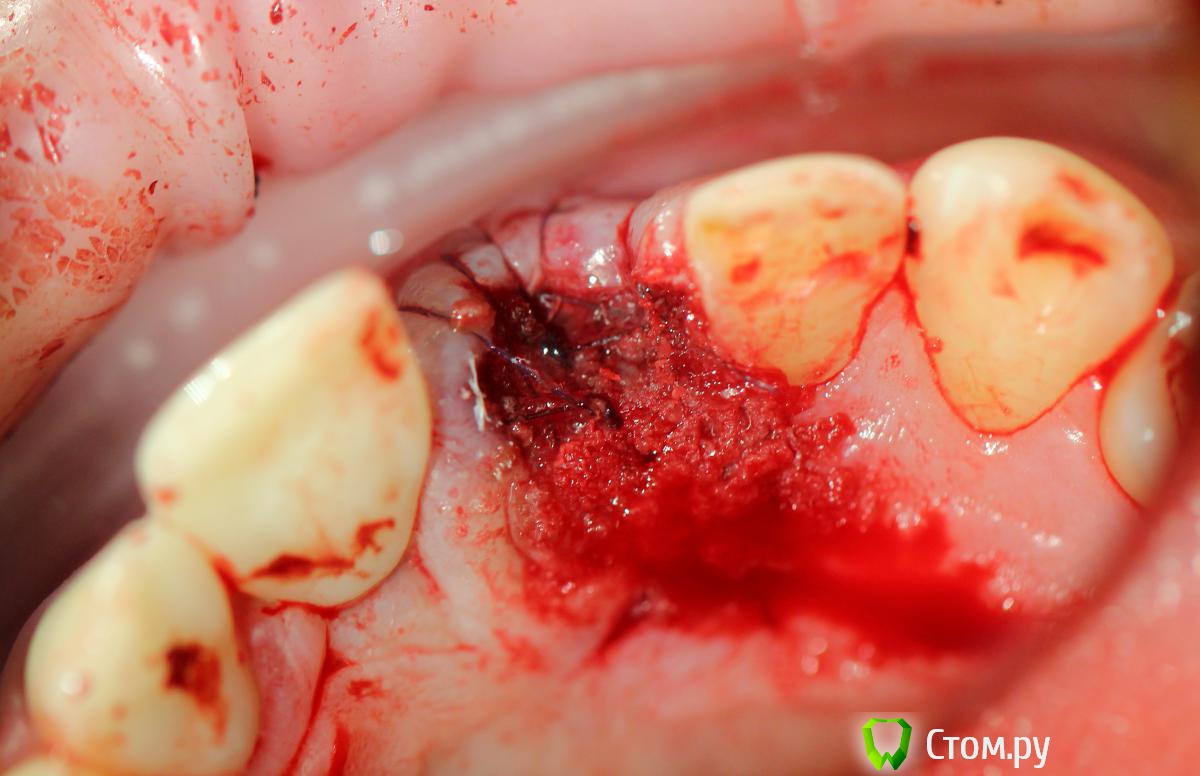

Andex Опубликовано 7 октября, 2014 Поделиться Опубликовано 7 октября, 2014 Внесу свой взгляд на тему. Мне интерестна методика - выкладываю свой кейс. Солидарен с Александром, если Вам интерестно - могу поделиться результатами и наблюдениями своих пациентов. На последнем фото - установил формирователь, тк через неделю после операции разошлись швы и сместился мною плохо мобилизованный ротированный(недостаточно) лоскут с неба - мои навыки еще далеки от идеала. Ссылка на комментарий

k.t.m. Опубликовано 7 октября, 2014 Поделиться Опубликовано 7 октября, 2014 у вас тут мега щит,прорезаться будет явно дольше)))) 2 1 Ссылка на комментарий